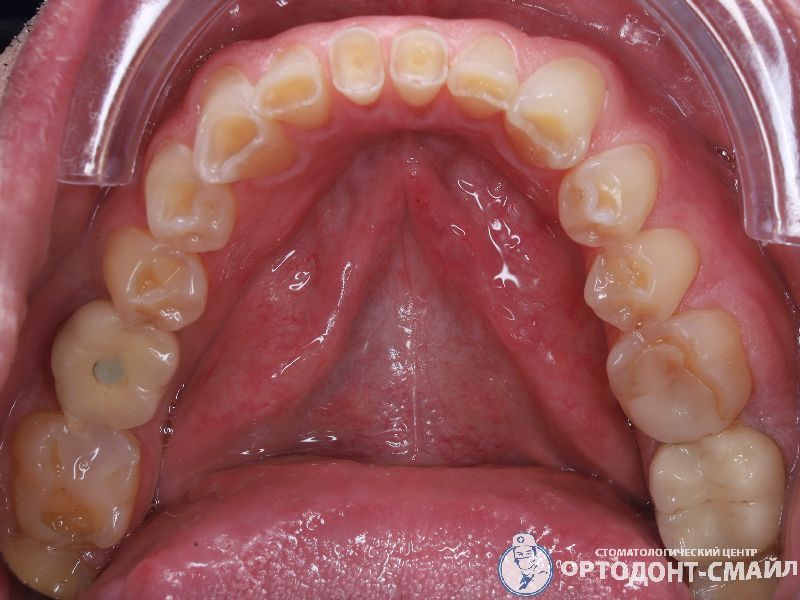

Диагноз: прямой травматический прикус, повышенная стираемость зубов.

Проведено: лечение ВНЧС, тотальная реабилитация по поднятию прикуса диоксидом циркона

нижняя челюсть